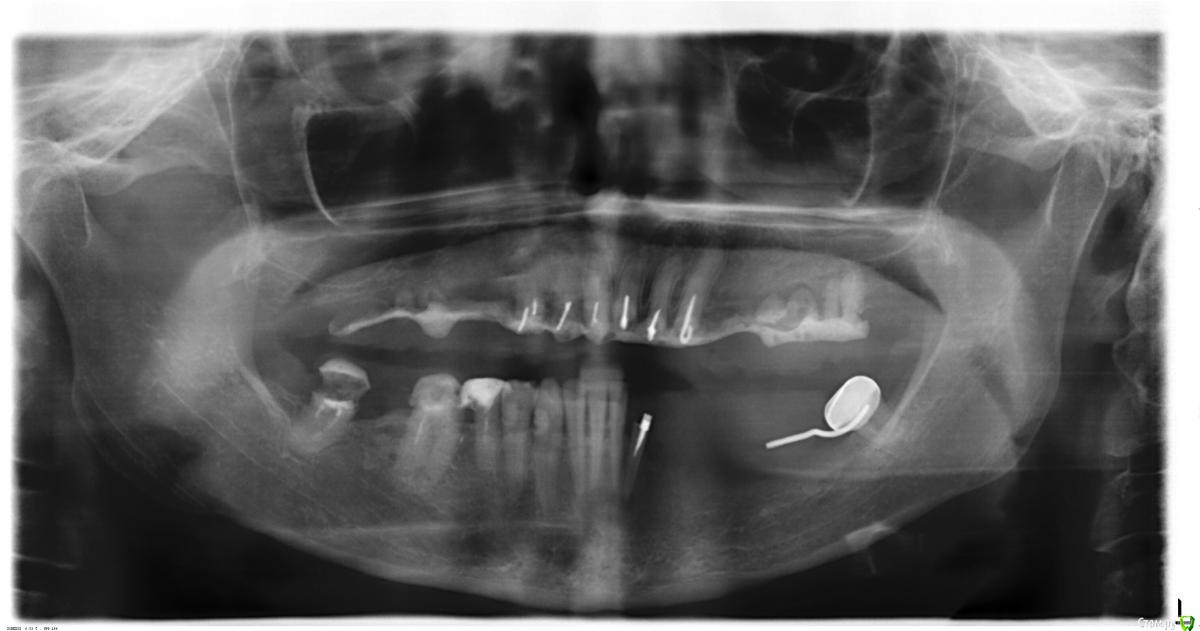

Белочка19 Опубликовано 6 августа, 2015 Автор Поделиться Опубликовано 6 августа, 2015 Вот снимок из этой клиники. Все что у меня есть. Ссылка на комментарий